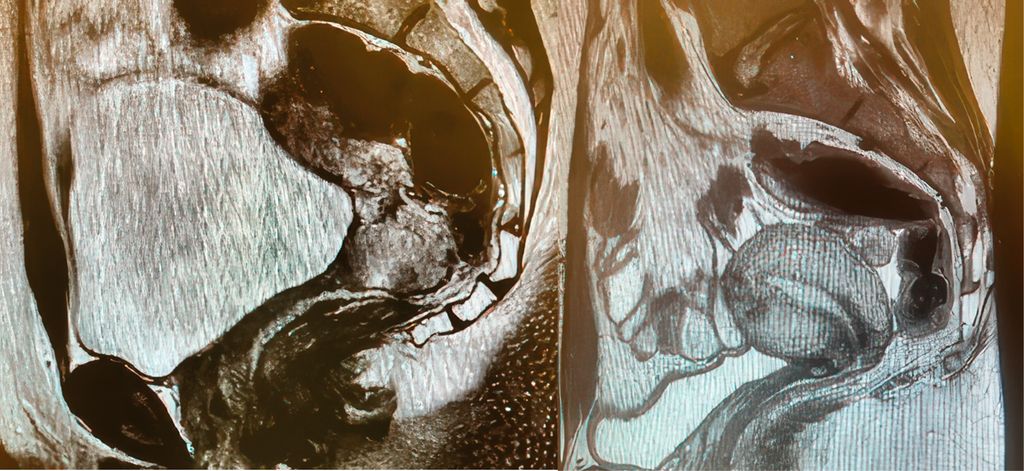

Bei nodal-negativen Tumoren mit einem Durchmesser zwischen 2 und 4cm können bei entsprechend motivierten Patientinnen ausserhalb der Leitlinien individuelle Therapieoptionen diskutiert werden, wie beispielsweise eine abdominale radikale Trachelektomie oder eine neoadjuvante Chemotherapie mit anschliessender Konisation (Abb. 1a und b).

Abb. 1: Präoperatives (a) und postoperatives (b) MRI des Beckens einer jungen nulligraviden Patientin im FIGO-Stadium IB2 mit einem Plattenepithelkarzinom der Zervix, die mit einer radikalen abdominalen Trachelektomie behandelt worden ist. Die Patientin ist drei Jahre nach der Behandlung tumorfrei